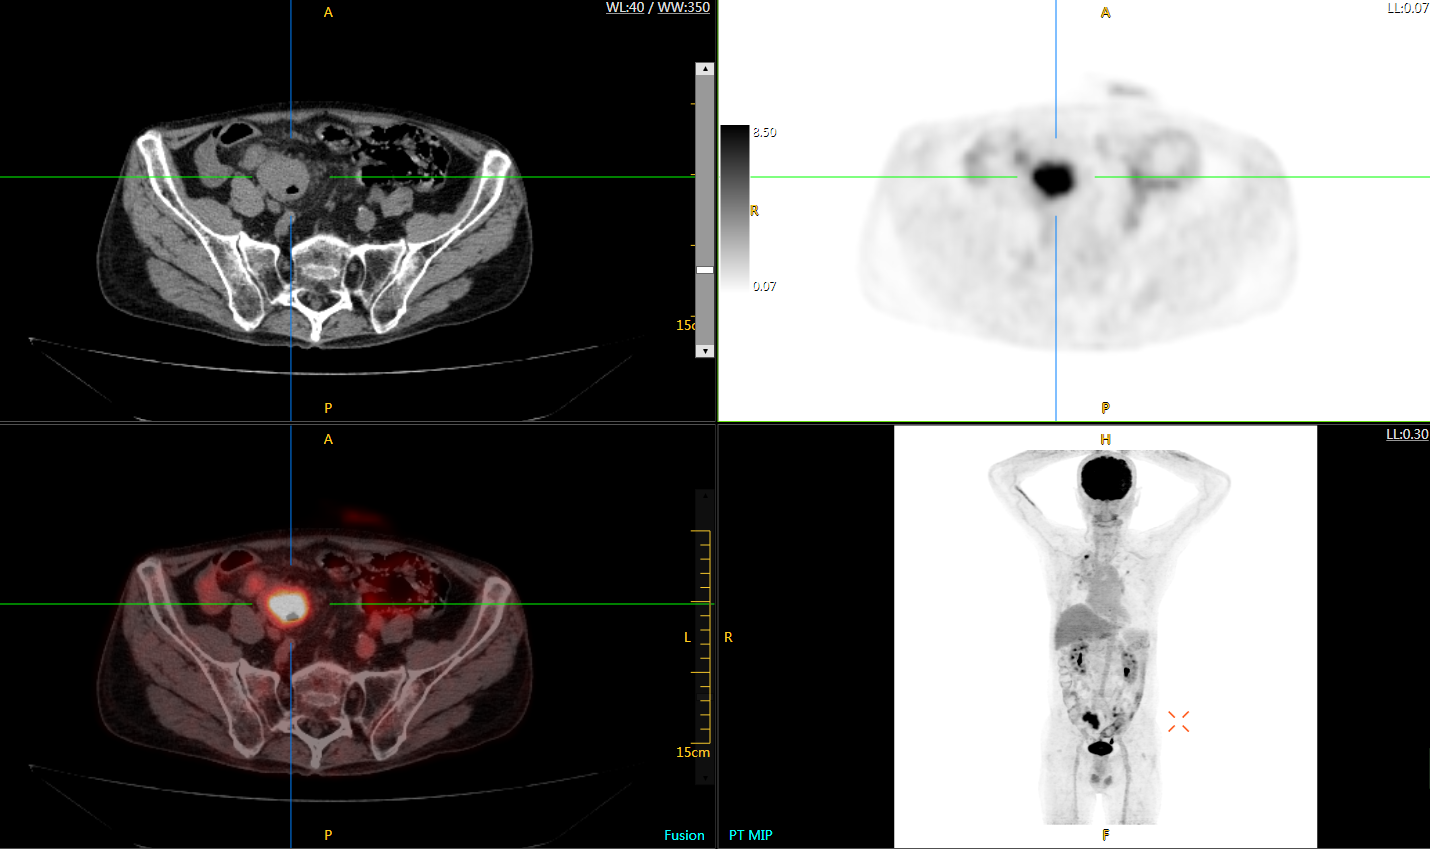

注射總劑量為0.67 mCi FDG(低于常規(guī)劑量的十分之一),基于uEXPLORER探索者掃描15分鐘的圖像

注射總劑量為6.9mCi,注射后10小時,基于uEXPLORER探索者掃描14分鐘的圖像